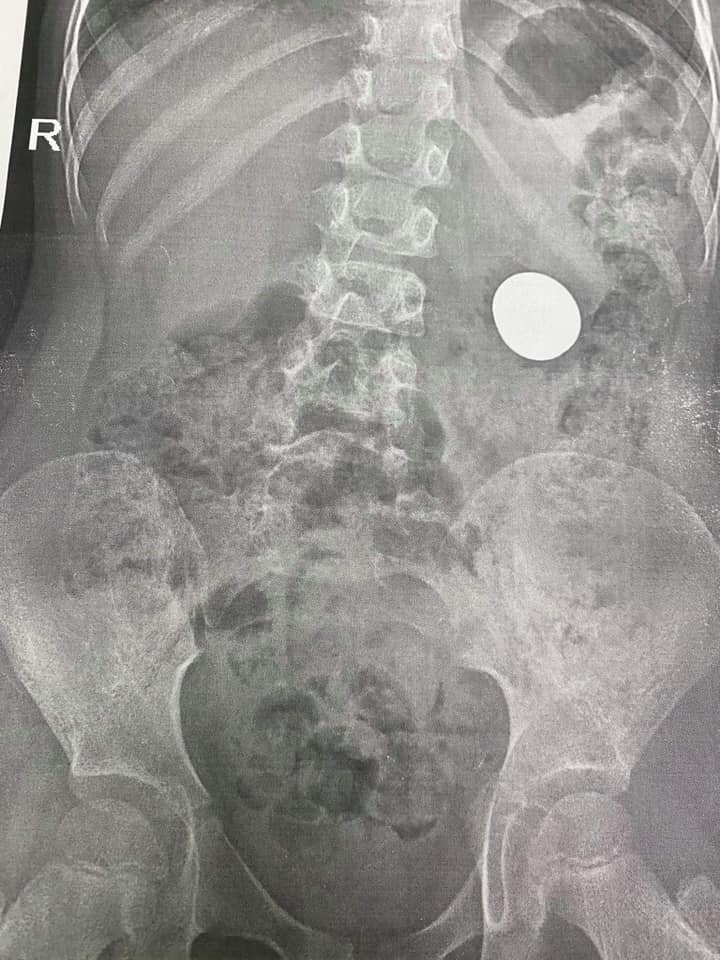

У Львові хірурги врятували життя 5-річній дівчинці, зі шлунку якої дістали копійки. Дитина проковтнула 2 монети. Читайте новини Львова на VG Львів.

Лікар-ендоскопіст діставала монети без операції за допомогою ендоскопа під наркозом.

“Це пост про найдорожчі у світі 2 гривні і 50 копійок! Їх діставали наші лікарі з шлунка 5-річної дівчинки. Раз монетка, два монетка… Малеча спробувала на зуб дві блискучі монетки і вони опинилися у її шлунку. Можна довго сперечатися про те, чому так сталося, але іноді навіть найтурботливіші у світі батьки можуть не вберегти своє янголятко”, — йдеться у дописі Львівської обласної дитячої клінічної лікарні ОХМАТДИТ у “Facebook”.

Операція була тривалою, бо у шлунку дівчинки була не 1 монета, а 2 — одна номіналом 2 гривні і друга 50 копійок.